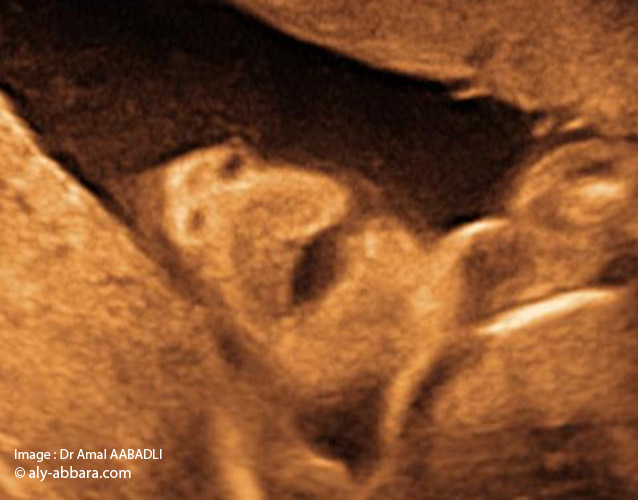

Coupe frontale de face : nez, bouche et menton_01

صورة الأنف الفم و الذقن

لا يكون إتمام فحص جنين ما دون فحص منطقة الأنف و الفم و الذقنً

يتم الحصول على هذه الصورة بقطعة تاجية للوجه و هذا يعني أن المسبار الصدوي يجب أن يوضع من الجبهة إلى الأسفل – نقول أيضاً قطعة جبهية و المعنى واحد- كأنه تاج. و يمكن أيضاً أن نوجهه من أسفل الذقن

هدف هذه الصورة هو التأكد من عدم وجود عَلَم شفهي

• La coupe échographique fœtale " nez, bouche et menton :

• L'étude morphologique du fœtus ne peut être complète sans l'examen de la région du "nez, bouche et menton".

• Pour obtenir cette image il faut effectuer une coupe coronale (frontale) sur la face, pour cela il faut diriger la sonde échographique posée sur le front du fœtus vers le bas du visage ; ou l'inverse, diriger la sonde posée sur le menton vers le haut du visage.

• Le but de cette image est de s'assurer de l'absence de fente labiale (bec de lièvre).